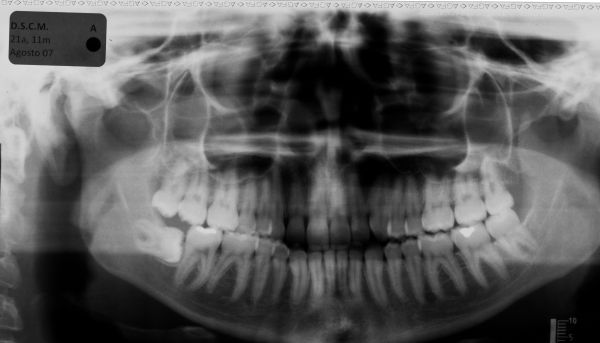

Tratamento da maloclusão de Classe III com elásticos intermaxilares e controle mecânico do arco inferior